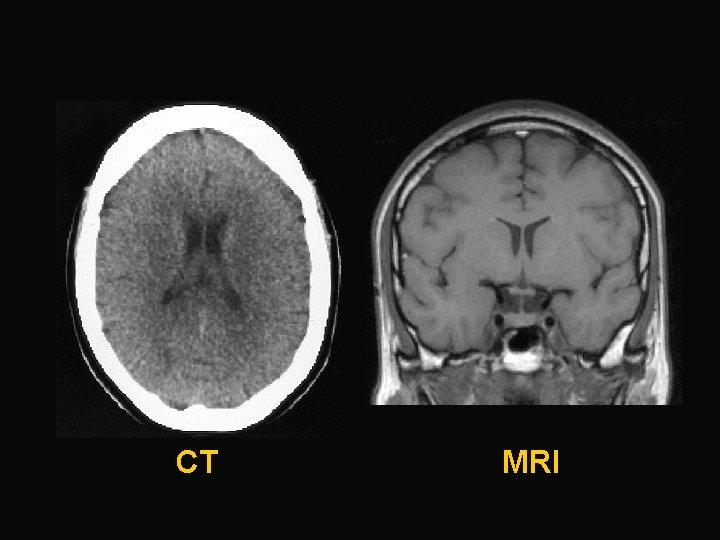

CT MRI

Hydrocephalus